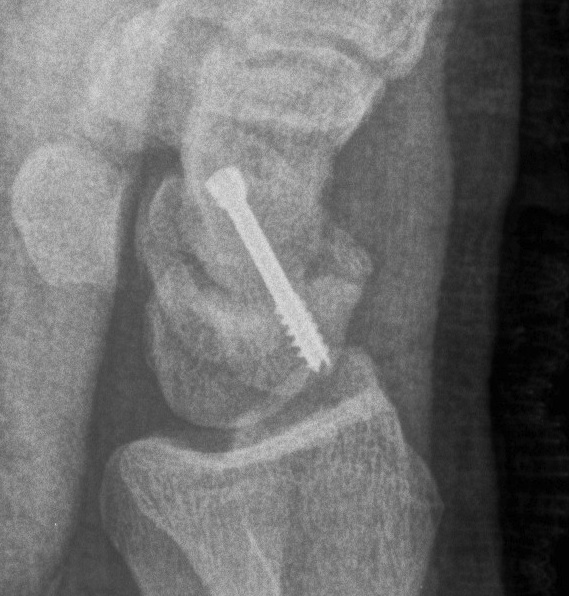

Scaphoid waist fracture 1 mm displaced

Scaphoid fracture with significant displacement

Scaphoid proximal pole fracture